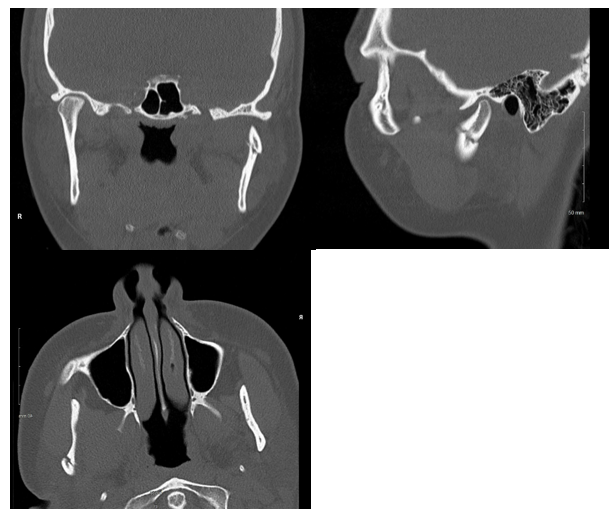

Figure 2 Non-contrast CT. Left to right, top to bottom; coronal, sagittal, and transverse views of the left mandibular condylar fracture.

A healthy, non-smoking, 22-year-old woman presented to the emergency department after suffering a fall from her bicycle. She was helmeted and denied any loss of consciousness or neck symptoms. Lower lip and chin lacerations were evident and she reported that her bite did not align. A noncontrast maxillofacial CT was obtained and showed a minimally displaced fracture of the right mandibular body and a minimally displaced fracture of the left mandibular condyle (Figures 1 & 2). Her soft tissues injuries were repaired and she was referred to the otolaryngology clinic for management of her fractures. Two days following the injury, the patient was evaluated in the clinic. She reported pain throughout the mandible in addition to trismus and mild malocclusion. The fractures were discussed and surgical treatment with ORIF and MMF was advised. An informed consent discussion occurred in which the risks and benefits of both the recommended treatment and no treatment were made clear. The patient expressed reasonable reservations about the surgery and opted for non-surgical management only. She was warned of the risks of non-union, malunion, and a potentially prolonged recovery period. Given her choice, she was strongly advised to visit the clinic on a weekly basis, adhere to a slowly progressing diet, and otherwise rest her jaw. The patient presented as mature and reliable and agreed to the plan.